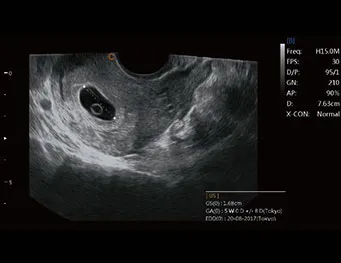

Sonda de TV de gran angular

● Ángulo extremadamente amplio de alrededor de 210°

● Proporcionar más información de diagnóstico

● Ahorre tiempo, mejore la eficiencia